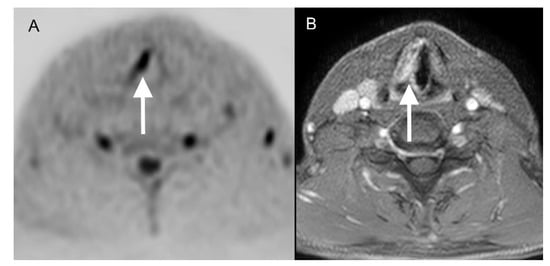

3.2. Findings of Standard MRI

3.3. Findings of DWIBS

3.4. Findings of Standard MRI + DWIBS